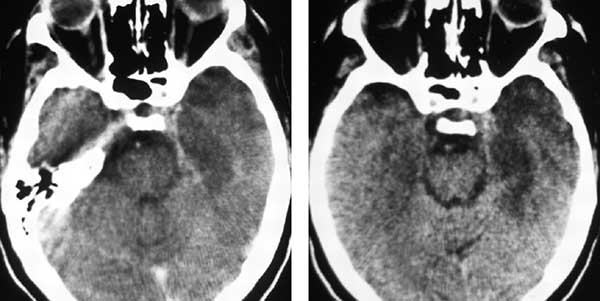

- يتم التشخيص بعمل صورة للدماغ بالتصوير المقطعي المحوسب CT، حيث تظهر فيه الأماكن الملتهبة والتي تحتوي على خراج على شكل مناطق غامقة اللون، ومحاطة بهالة فاتحة.